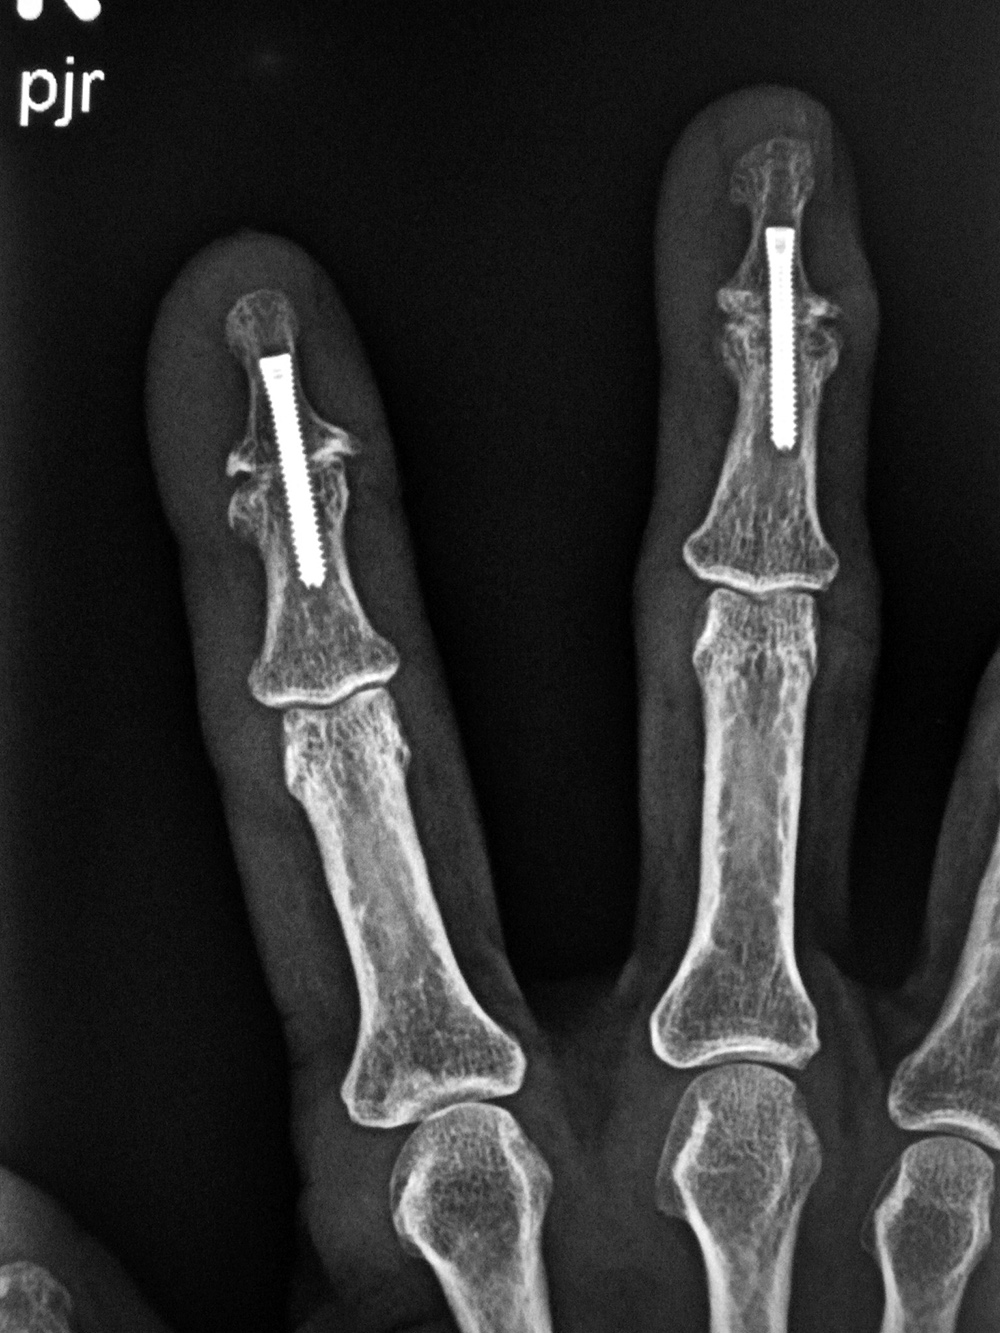

A similar screw is the Acutrak screw. It is headless with variable thread pitch on either end, but it does not have an unthreaded central shank (figure: Acutrak screw) (figure: Acutrak screws and endobuttons). It is very commonly used for the treatment of finger and wrist fractures. The Smart (toe) implant is a product of Stryker specifically designed for interdigital fusion of fingers or toes and other small bones. It is sometimes used in conjunction with K-wires and small fixation screws (figure: Smart toe implants).

| Accutrak screws

| The Accutrak screws are used for arthrodesis of the distal interphalangeal joints of the right index and long fingers in a woman with severe osteoarthritis.